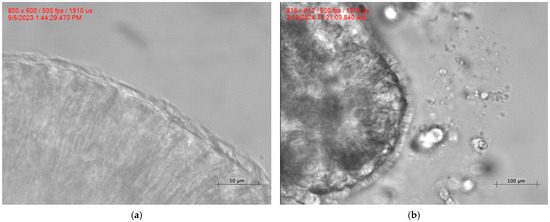

Cilia Dynamics in Primary Ciliary Dyskinesia: A Biophysical Characterization of the RSPH4A Founder Variant

Primary ciliary dyskinesia (PCD) is a rare ciliopathy resulting in chronic oto-sino-pulmonary disease. PCD diagnosis can be achieved by a combination of different diagnostic and adjuvant tools, including high-speed video-microscopy analysis (HSVA). A founder variant has been described in Puerto Rico as the [...] Read more.

Primary ciliary dyskinesia (PCD) is a rare ciliopathy resulting in chronic oto-sino-pulmonary disease. PCD diagnosis can be achieved by a combination of different diagnostic and adjuvant tools, including high-speed video-microscopy analysis (HSVA). A founder variant has been described in Puerto Rico as the most common cause of PCD in the island. Background/Objectives: In HSVA, objective parameters such as ciliary beat frequency (CBF) and subjective parameters such as ciliary beat pattern (CBP) shed light on the biophysical properties of cilia. However, the subjective nature of CBP creates a gap in knowledge; characteristics such as the length, angle, and bending index of cilia are poorly described. Our goal is to quantify cilia dynamics of the RSPH4A (c.921+3_921+6delAAGT (intronic)) founder variant in Puerto Rico through biophysical properties of cilia. This approach enhances longitudinal patient care by understanding treatment progress through biophysical ciliary function. Methods: We analyzed images from HSVA of six patients with PCD homozygous for the founder variant and six healthy controls (HC) (n = 12). Results: We found that ciliary length (PCD = 7.62 ± 0.95 μm, HC = 8.12 ± 1.36 μm, p = 0.204 ns), orientation vector (PCD = 7.20 ± 0.93 μm, HC = 7.25 ± 1.01 μm, p = 0.883 ns), straight angle (PCD = 1.67 ± 0.27 rad, HC = 1.76 ± 0.29 rad, p = 0.380 ns), and area (PCD = 2.35 ± 0.52 μm2, HC = 2.10 ± 0.53 μm2, p = 0.264 ns) did not have statistically significant differences between PCD and HC. In contrast, bending index (PCD = 1.06 ± 0.04, HC = 1.12 ± 0.09, p = 0.01), bent angle (PCD = 1.11 ± 0.30 rad, HC = 0.67 ± 0.21 rad, p < 0.0001), net angle (PCD = 0.56 ± 0.26 rad, HC = 1.09 ± 0.35 rad, p < 0.0001), amplitude (PCD = 5.77 ± 1.25 μm, HC = 7.99 ± 1.65 μm, p < 0.0001), and amplitude per second (PCD = 48.83 ± 13.23 A(s), HC = 91.66 ± 27.96 A(s), p < 0.0001) showed significant differences between both groups. Conclusions: Reduced angular excursion and amplitude in PCD demonstrate that the beating pattern of the RSPH4A founder variant is dysfunctional as compared with healthy controls. Our study provides an objective framework to understand the biophysical properties of the RSPH4A founder variant. Full article

(This article belongs to the Special Issue The Role of Cilia in Health and Diseases—2nd Edition)

Show Figures

Figure 1